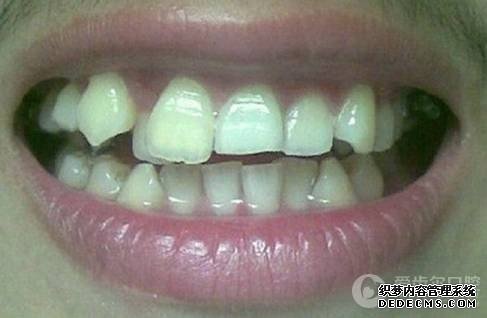

患者自述:眼看快到而立之年,身边好友都已成家立业,可我依然孤身一人,难免有些落寞。可是因为牙齿不齐,让我总是缺乏自信,性格也变得内向腼腆,几次相亲都被心仪的女孩拒绝。为了不被自卑心吞噬,我决定通过牙齿正畸改变自己,给自己一次幸福的机会。

临床诊断:通过3D数字化全景机的拍片检查,患者上下牙排列拥挤,前牙受挤压向内歪斜,咬合关系异常,唇形尚可,颞下颌关节检查未见异常,无蛀牙、牙周疾病症状。经过和患者商量,选定自锁托槽矫正方案,调整牙间隙,恢复牙齿的正常排列,实现正常的咬合关系。

矫正前照片